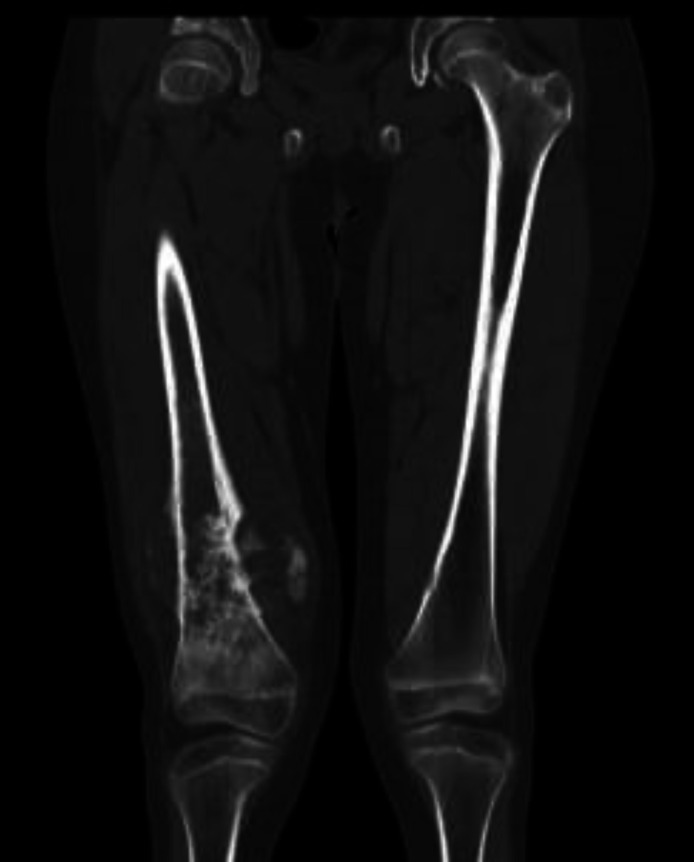

Case presentation: In this study, we present the case of a 16-year-old male patient with of osteosarcoma of the right femur with pulmonary metastasis, who received ifosfamide as part of chemotherapy 1 year and 2 months ago and required hospitalization for cellulitis. During inpatient management, he presented with hypokalemia, hypophosphatemia, polyuria, glycosuria, and proteinuria, by which he was diagnosed with Fanconi syndrome and nephrogenic diabetes insipidus, induced by ifosfamide. Management was focused on the control of the internal environment and use of potassium supplements and potassium-sparing diuretics.